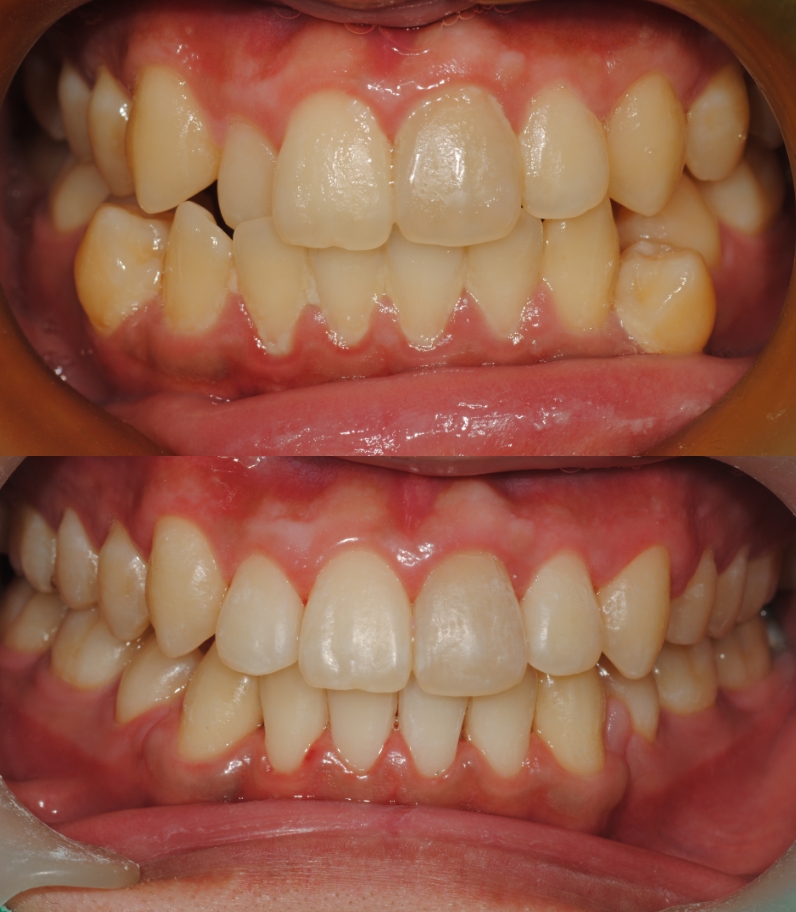

치아교정 전/후

실제 케이스

소아 교정부터 성인 교정까지 환자분들의

상황과 상태에 맞는

올바른 치료를 위해

끊임 없이 연구하고 고민합니다.

로그인 후 모든 치료후기를 살펴보세요.

치아교정

치료기간 : 2023.05 - 2024. 09 (1년 4개월)